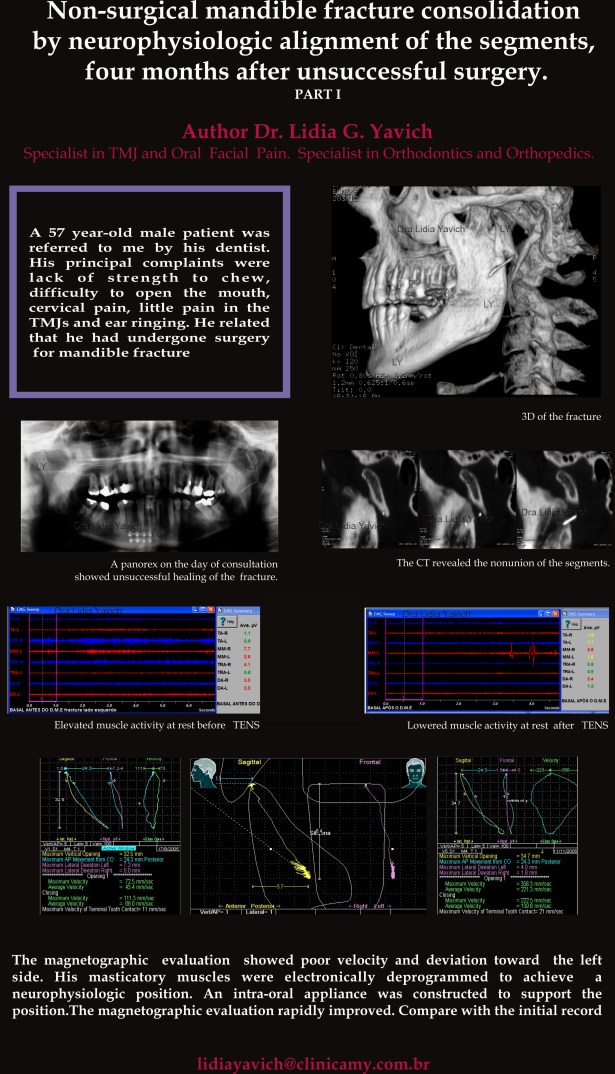

O presente caso clínico documenta um paciente do sexo masculino de 57 anos de idade com uma complicação por falta de união do côndilo mandibular esquerdo quatro meses após a cirurgia e a resolução deste caso com um alinhamento neuromuscular fisiológico dos segmentos, sem uma nova cirurgia ou fixação interna.

Paciente do sexo masculino de 57 anos de idade foi encaminhado para a clínica por seu dentista. Suas principais reclamações foram: falta de força ao mastigar, dificuldade em abrir a boca, dor cervical, dor nas ATMs e zumbido no ouvido esquerdo.

A história clínica revelou que o paciente caiu no banheiro quatro meses antes da consulta, batendo o queixo e fraturando sua mandíbula. Ele foi cirurgicamente tratado para a fratura da sínfise e do côndilo mandibular esquerdo.

Após a realização de todas as avaliações clínicas foi solicitado uma radiografia panorâmica. Foi evidente a falta de união da fratura do côndilo mandibular esquerdo.

Foi solicitada uma TC (tomografia computadorizada) para obter um diagnóstico mais preciso.

TC: cortes sagitais confirmando a falta de união total da fratura do côndilo mandibular, quatro meses após a cirurgia.

Reconstrução em 3D mostrando a falta de união total da fratura do côndilo mandibular, quatro meses após a cirurgia.

Registro eletromiográfico antes da desprogramação eletrônica na primeira consulta: atividade elevada do masseter direito, do trapézio direito e do digástrico direito em repouso.

Todos estes músculos mastigatórios abaixaram os seus valores após a desprogramação eletrônica.

Diminuição da atividade dos músculos mastigatórios em repouso após a desprogramação eletrônica.

Foi utilizada estimulação elétrica transcutânea neural (TENS) da divisão mandibular do nervo trigêmeo (V) para relaxar os músculos mastigatórios e registrar a posição de repouso da mandíbula.

Essa posição de repouso mandibular tridimensional foi gravada sob a forma de um registro de mordida oclusal, que mais tarde foi utilizado para fabricar um dispositivo intraoral.

Este é um aparelho removível mandibular que, neste caso, deve ser usado durante o dia e a noite pelo paciente.

Este aparelho intraoral é testado eletromiograficamente e cinesiograficamente para suportar esta posição neuromuscular fisiológica.

A habilidade de posicionar espacialmente a mandibula, através da medição do comprimento de repouso dos músculos mastigatórios pode ser um auxiliar importante na recuperação das fraturas do côndilo mandibular.